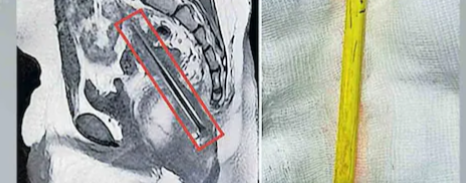

‘കാണാതായ’ പെൻസിൽ കഷണം എവിടെയെന്ന ചോദ്യത്തിനുള്ള ഉത്തരം ആ എക്സ്റേയിലുണ്ടായിരുന്നു. പെൽവിസിനുള്ളിൽ ഏകദേശം 12 സെന്റീമീറ്റർ നീളത്തിൽ അതു കിടക്കുന്നു. പെൻസിലിന്റെ മൂർച്ചയുള്ള ഭാഗമുണ്ടായിരുന്നിട്ടും ശരീരത്തിലെ പ്രധാന രക്തക്കുഴലുകൾക്കൊന്നും അതു ക്ഷതമേൽപ്പിക്കാതിരുന്നതു ഭാഗ്യമായി– ഡോ. ജോണി വാകയിൽ ഫ്രാൻസിസ് പറഞ്ഞു. അൾട്രാസൗണ്ട്, എംആർഐ പരിശോധനയിലൂടെ പെൻസിലിന്റെ കൃത്യമായ സ്ഥാനം കണ്ടെത്തി. സീനിയർ പീഡിയാട്രിക് സർജൻ ഡോ. എം.ജി. ജോയിയുടെ നേതൃത്വത്തിലുള്ള സംഘം ശസ്ത്രക്രിയയിലൂടെ പെൻസിൽ പുറത്തെടുത്തു. ഇത്ര വലിയ വസ്തു 4 മാസം ശരീരത്തിനുള്ളിലിരുന്നിട്ടും മറ്റൊരു ആരോഗ്യ പ്രശ്നവുമുണ്ടായില്ലെന്നതു ഡോക്ടർമാർക്ക് അദ്ഭുതം.